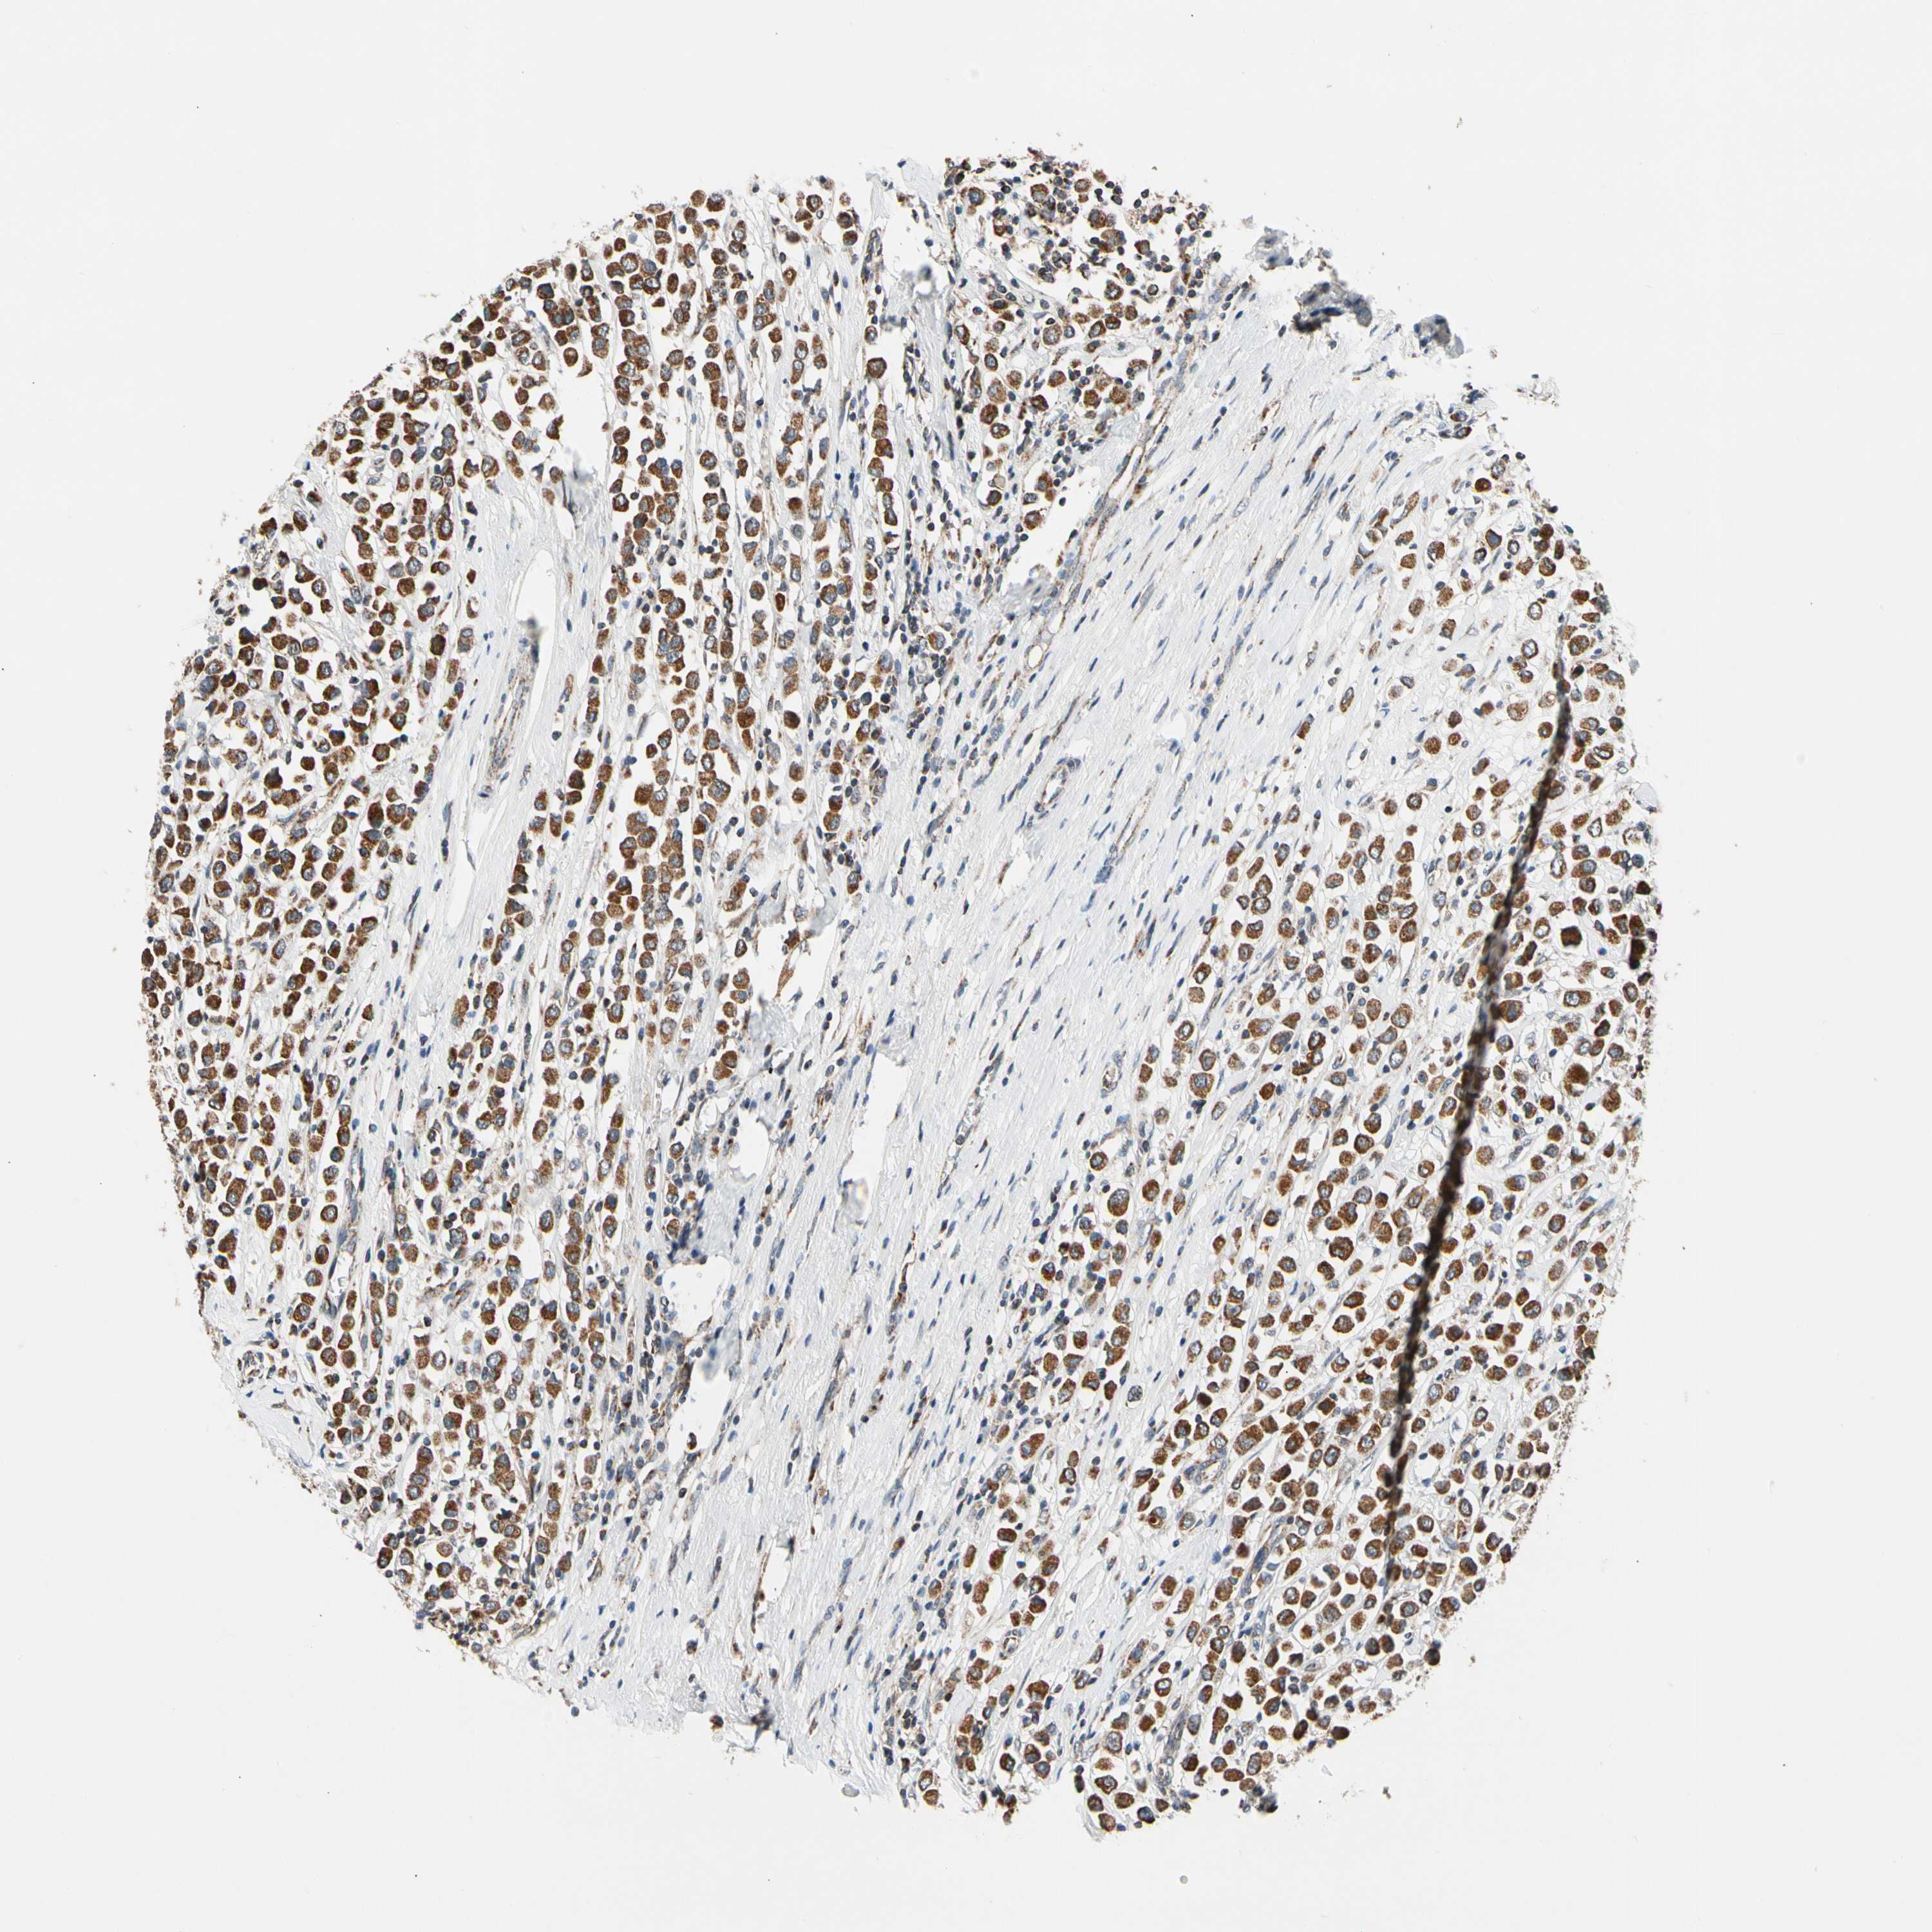

BRCA TCGA BRCA VALIDATION PROTEIN EXPRESSION

Breast cancer

Human cancer